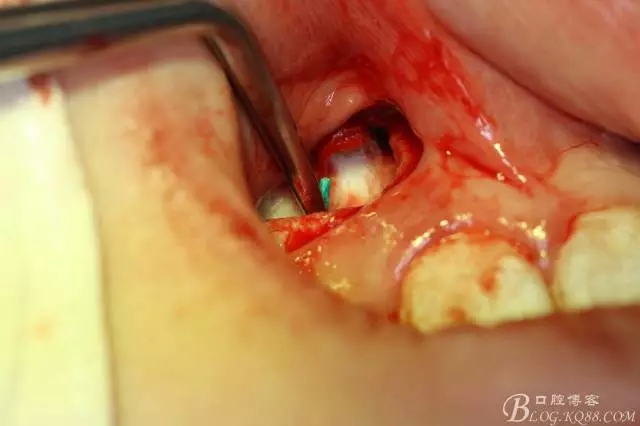

病例資料: 患者、柴xx、女、16歲。??茩z查及病歷如下圖: 患者同意我院正畸科建議,遂轉(zhuǎn)診倒外科。術(shù)前簽知情同意書。 治療過程: 圖1.術(shù)前的CBCT檢查:13阻生,疑為含牙囊腫??v剖面顯示12牙根吸收至根尖1/3。 圖2.局部麻醉下 。行唇側(cè)弧形切口,12松動(dòng)不到1°。 圖3.翻瓣、暴露骨面。 圖4.去骨、 暴露13牙冠 圖5.去骨、逐漸顯露13。 圖7.拔除13. 圖8.摘除囊壁 圖9.必須完整剝離囊壁。 圖10.摘除囊壁后形成的骨腔 圖11.超聲骨刀12根尖倒預(yù)備 圖13. 消毒棉球骨腔內(nèi)隔濕血液,紙尖干燥倒預(yù)備好的根管 圖14. 紙尖無血即可 圖15。MTA倒充填 圖16.骨腔填塞膠原蛋白海綿 圖17.拔除的13及摘除的囊壁 圖18.縫合 圖19.術(shù)后x線根尖片影像:MTA封閉根尖